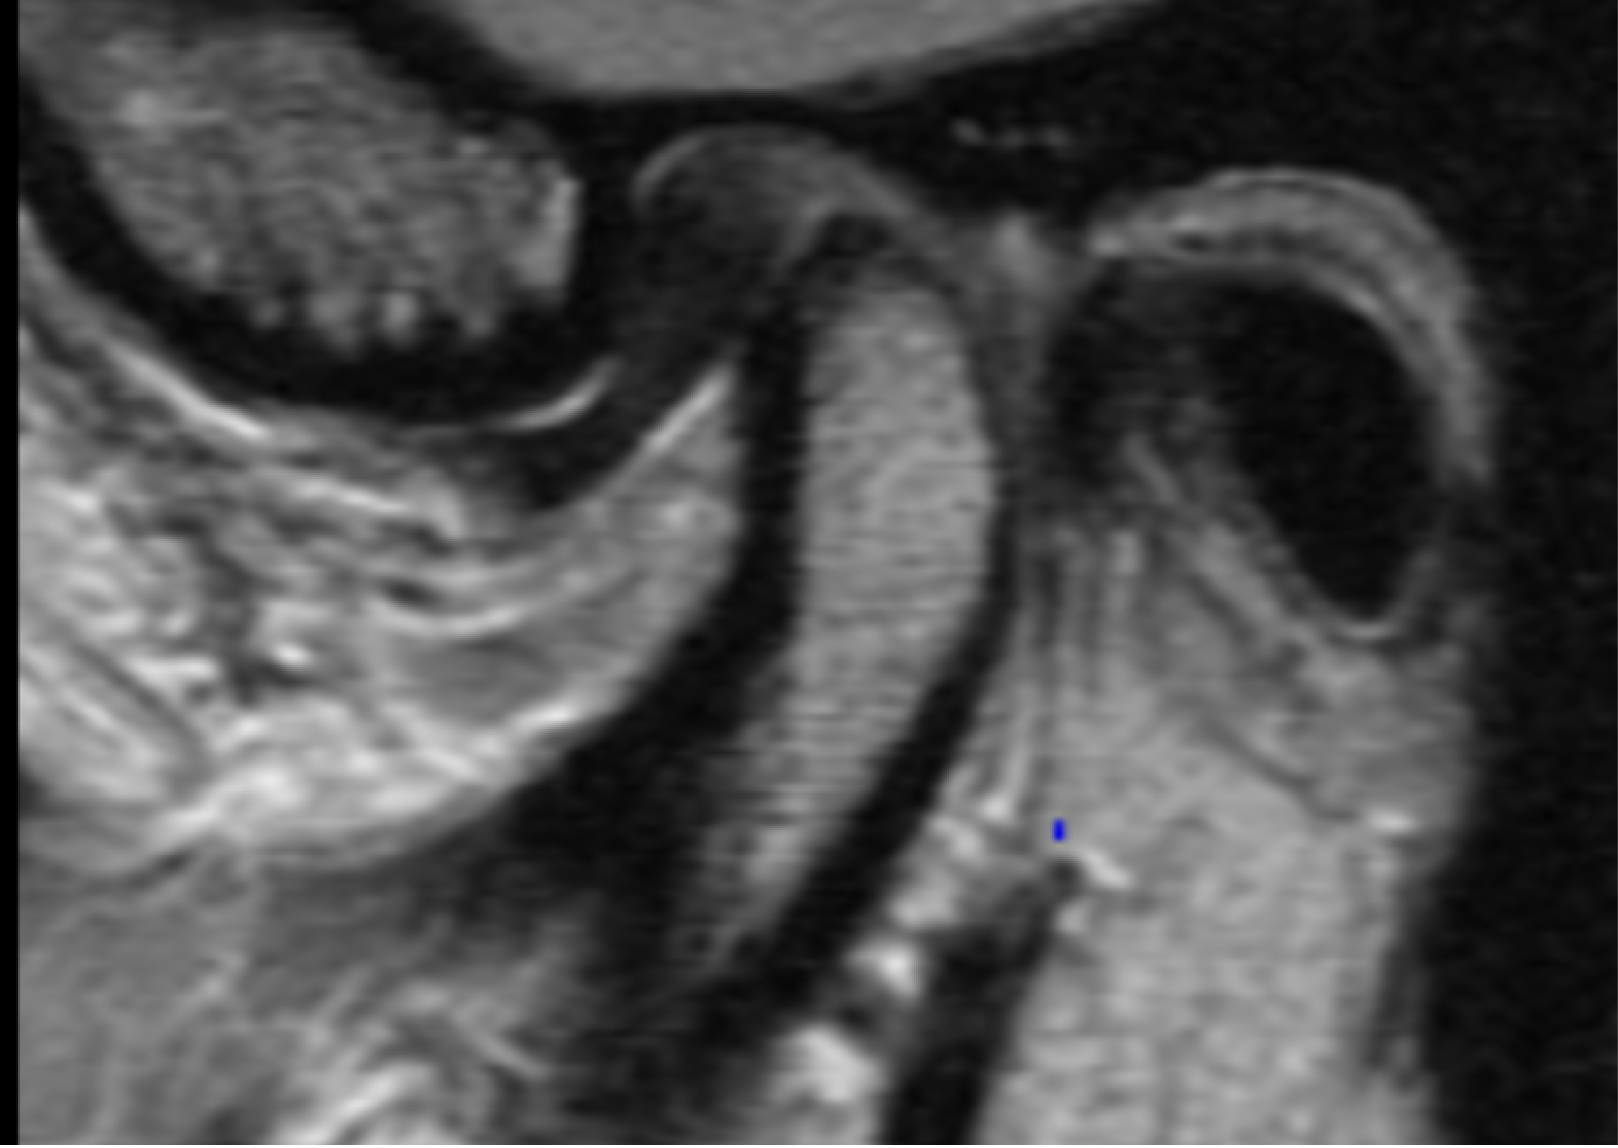

MRI Imaging Evaluation